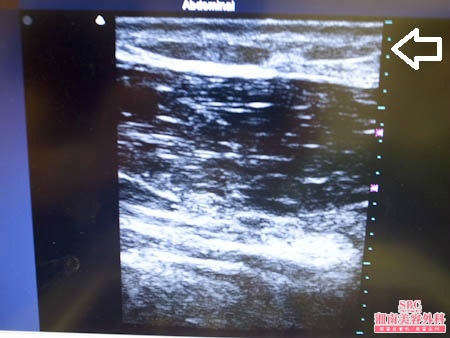

No.120413【脂肪吸引】圧倒的吸引量で圧倒的満足度!あの有名な根こそぎ竹田先生の劇的ビフォーアフター!〜バレーボールで鍛えた筋肉質な二の腕を根こそぐ!術中3Dタッチビュー〜